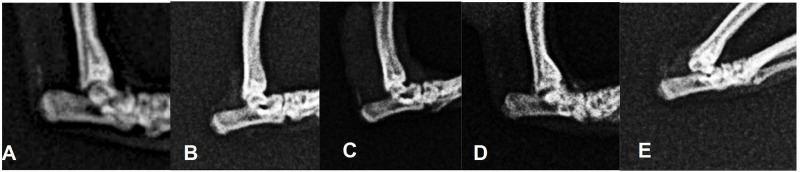

Methods: Twenty male Sprague-Dawley rats were assigned into five groups, consisting of one control group, and four diabetic groups which were induced by STZ injection and a high-fat diet. Among these diabetic rats, two groups received complete Freund's adjuvant (CFA) injections to the left ankle of the hind limb. The control group, one of the diabetic-only groups, and one of the arthritic-diabetic-induced groups were euthanized at 4 weeks after STZ induction, and the remainder were euthanized 6 weeks after STZ induction. Clinical, radiological, and histological examinations were then compared in all five groups.

Results: Diabetic status was successfully achieved in the model, which was maintained until the completion of the study. The CFA-induced ankles were significantly larger than the contralateral ankles in all groups (p<0.05). Histopathological evaluation confirmed arthritic changes in the CFA-induced group with less variability after 4 weeks of arthritis induction.